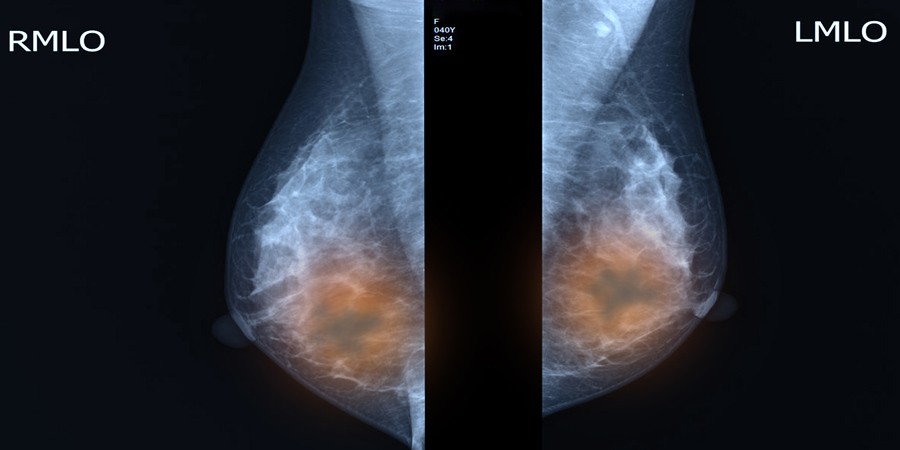

[Figuur 2] toont voor alle kankersoorten het aandeel van tijd gespendeerd bij de huisarts (HI), voor de verschillende kwartielen van de totale DI-duur. Voor colorectale kanker neemt bij een langere duur van het diagnostisch interval de proportie gespendeerde tijd bij de huisarts toe.

Figuur 2 | Het aandeel van het huisartsinterval, als percentage van de totale duur van het diagnostisch traject